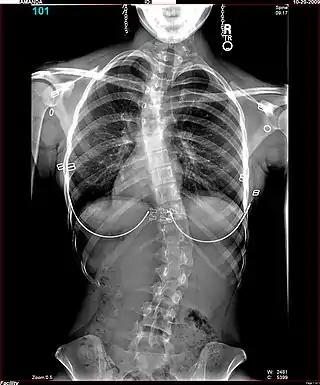

Es habitual que cuando se sospecha de escoliosis, se tomen radiografías del tórax en planos anteroposterior/coronal, y lateral/sagital, para evaluar las curvas de la escoliosis, además de las curvas normales de cifosis y lordosis, ya que estas también pueden estar afectadas en personas con escoliosis. Los rayos X de la columna en un paciente de pie, son el método estándar para evaluar la severidad y progresión de la escoliosis, y si es de naturaleza congénita o idiopática. En individuos en crecimiento, las radiografías seriales se obtienen en intervalos de 3-12 meses para seguir la progresión de la curvatura, y en algunos casos, se necesita además de resonancia magnética para examinar la médula espinal.

El método estándar para evaluar cuantitativamente la curvatura es la medida del ángulo de Cobb, el cual es el ángulo entre dos líneas, dibujado perpendicularmente a la placa terminal superior de la vértebra más superior involucrada y la placa terminal inferior de la vértebra más inferior afectada. Para los pacientes que tienen dos curvas, los ángulos de Cobb se siguen para ambas curvas. En algunos pacientes, se obtienen rayos X con inclinación lateral para evaluar la flexibilidad de las curvas o las curvas primaria y de compensación.